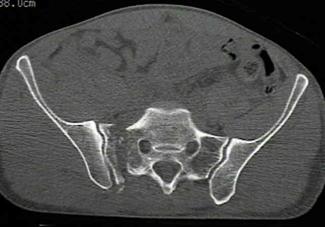

Compresie laterala

Fracturi pelviene multiple Fracturi pelviene multiple

Compresie bilaterala Compresie bilateralaAspect CT

Fracturi pelviene multiple Fracturi bilaterale de ramuri pubiene

Compresie bilaterala Aspect CT Disjunctie sacro-iliaca stanga Compresie antero-posterioara